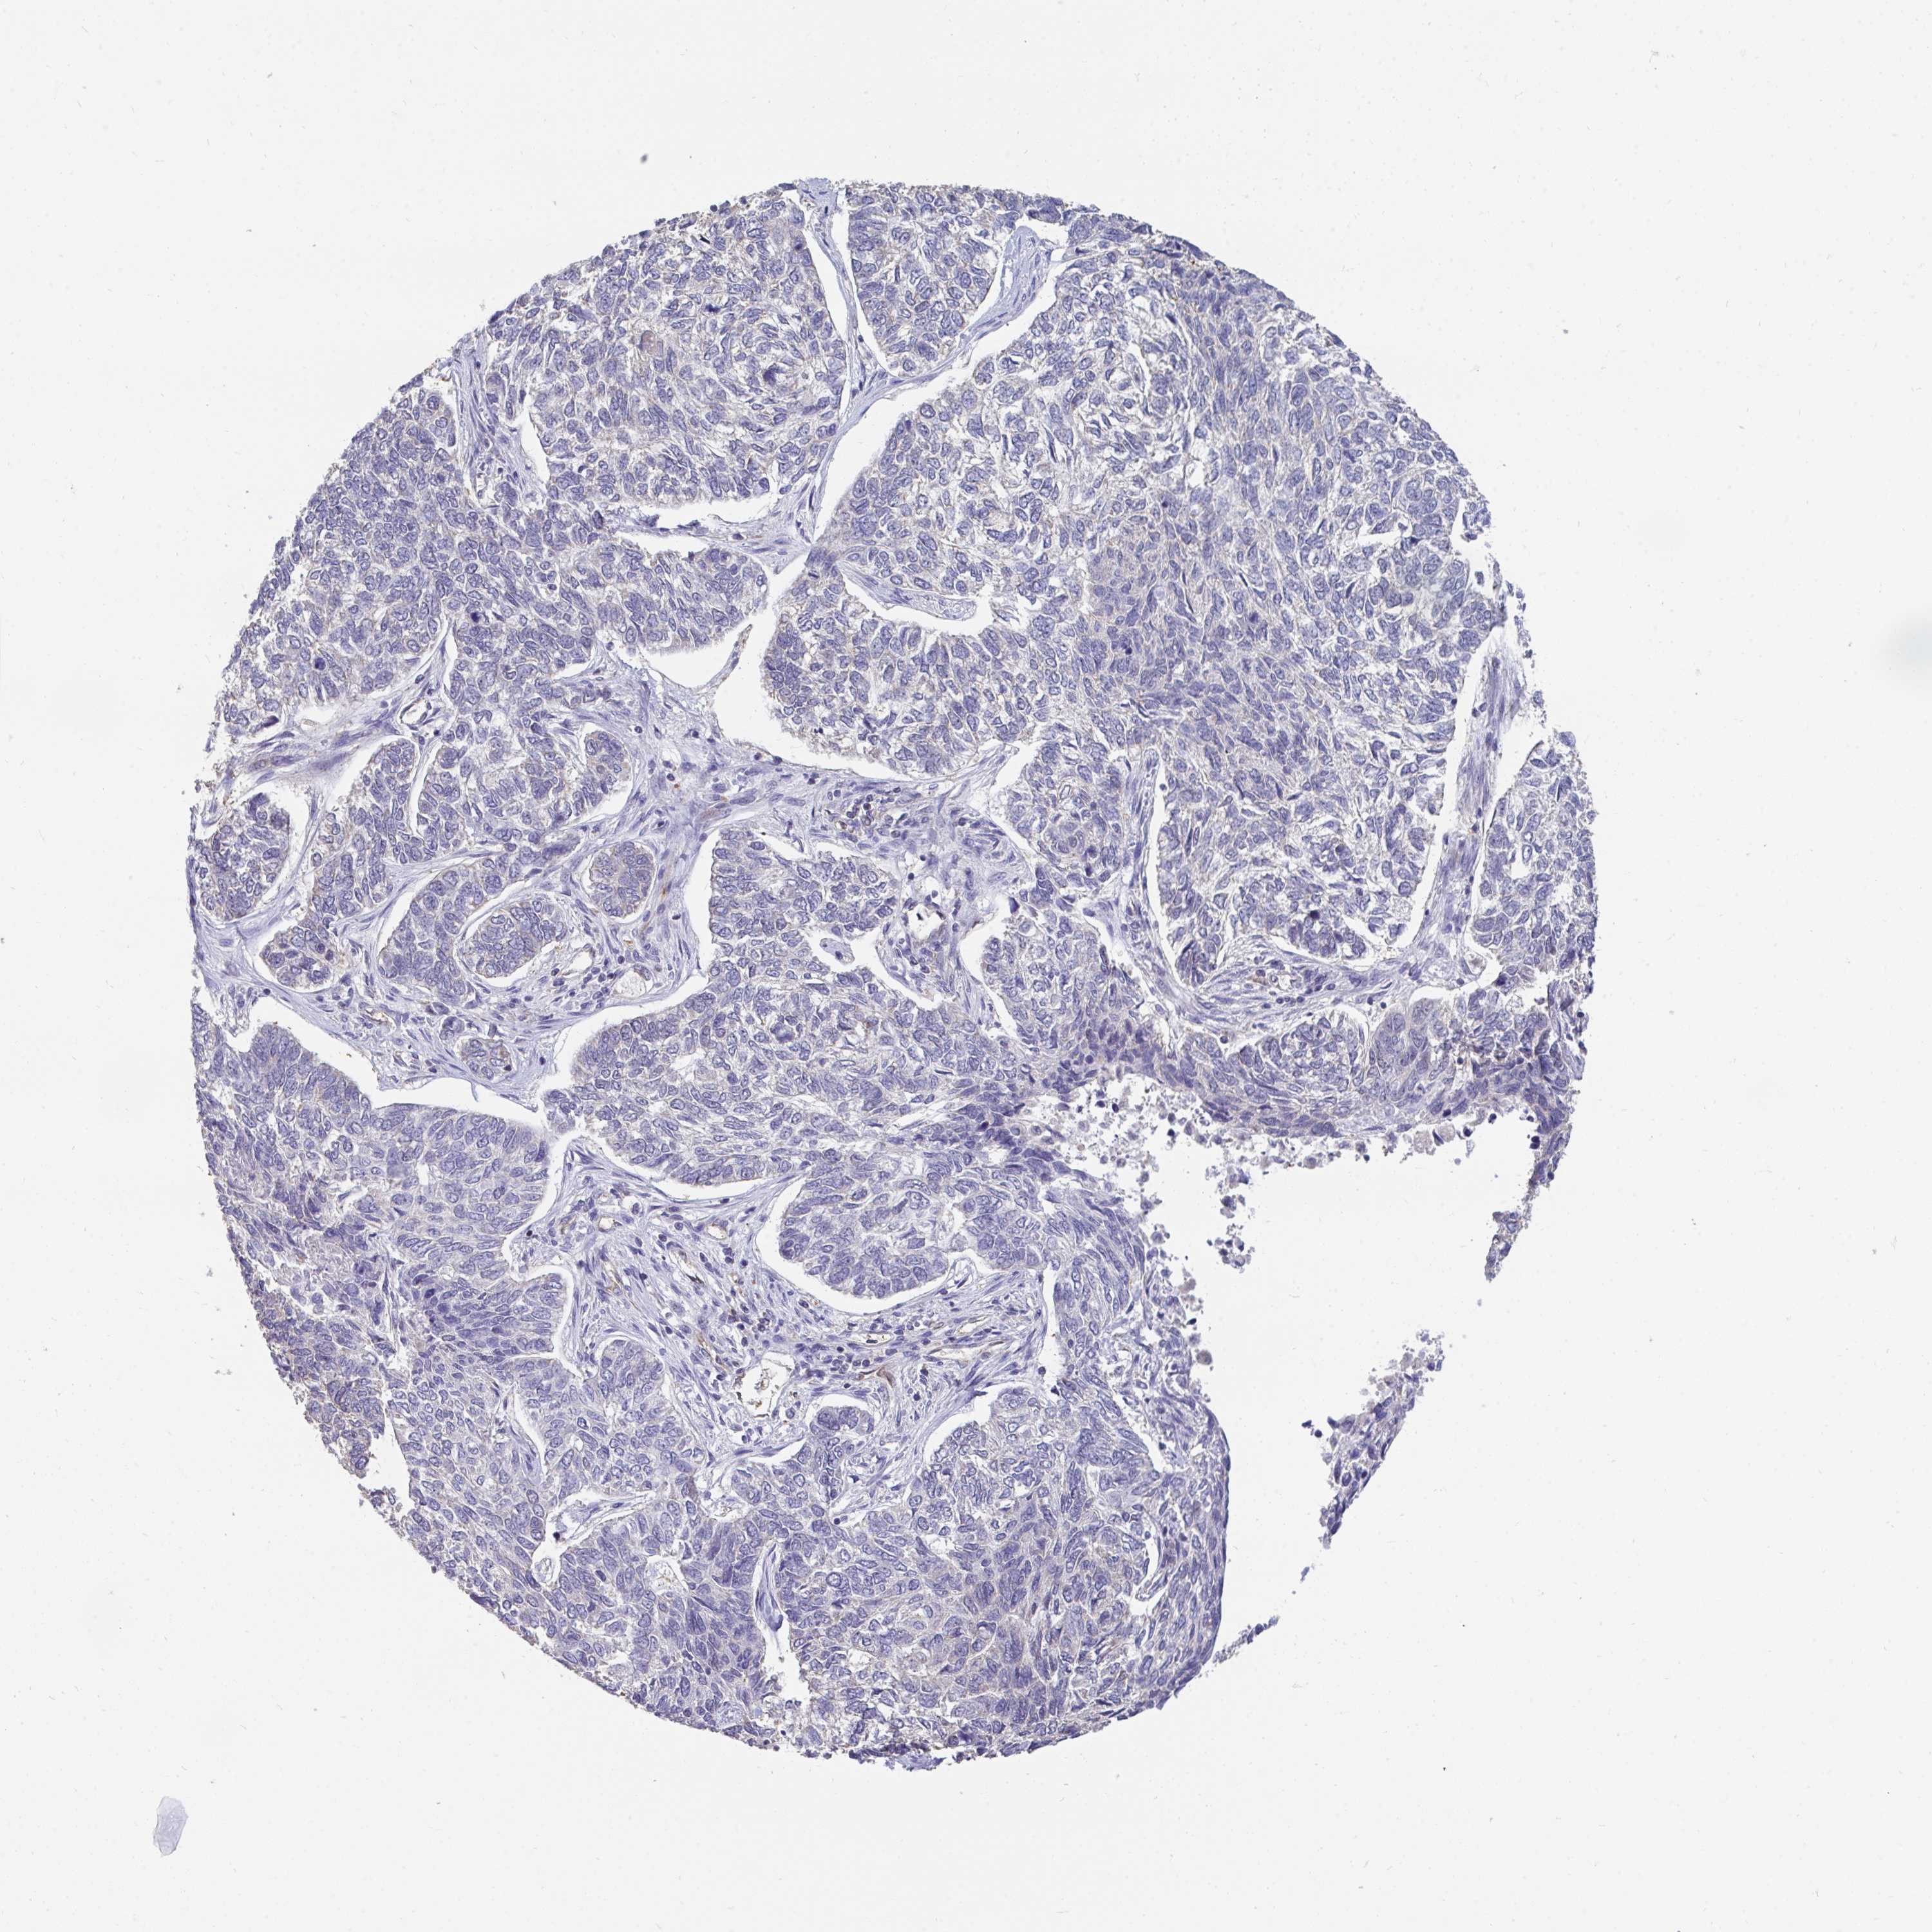

SKIN CANCER - Protein expressioni

A mouse-over function shows sample information and annotation data. Click on an image to view it in a full screen mode. Samples can be filtered based on level of antibody staining by selecting one or several of the following categories: high, medium, low and not detected. The assay and annotation is described here.

Antibody stainingi

Antibody staining in the annotated cell types in the current human tissue is reported as not detected, low, medium, or high, based on conventional immunohistochemistry profiling in selected tissues. This score is based on the combination of the staining intensity and fraction of stained cells.

Each image is clickable and will lead to virtual microscopy that enables deeper exploration of all samples and also displays staining intensity scores, fraction scores and subcellular localization as well as patient and tissue information for each sample.

Antibody HPA060290

Staining

High

Strong

Quantity

Location

Basal cell carcinoma

Squamous cell carcinoma, NOS